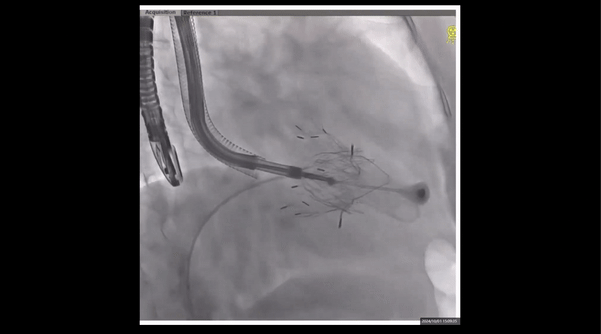

術(shù)前右室造影

夾持件位置確認(rèn)

室間隔位置確認(rèn)

術(shù)中經(jīng)食道超聲輔助下可見LuX-Valve Plus夾持件抓捕瓣葉狀態(tài)良好,夾持件在位,室間隔錨定位置良好,假體瓣膜整體錨定狀態(tài)穩(wěn)固。